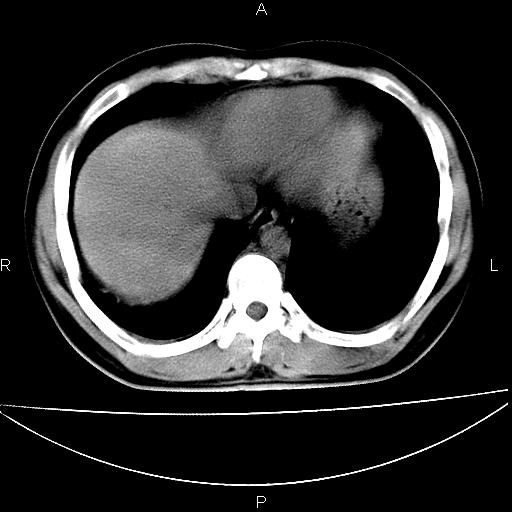

男 25岁 自述 尿频尿急,排尿困难20多天.无腰痛, b超说左肾盂轻度积水,左输尿管上端扩张.未见结石影. ct我看双侧肾盂轻度积水,双输尿管上端都扩张,大家看看能看见结石吗?

双肾轻度积水,双侧输尿管上段扩张(原因待查)。

双输尿管扩张下端未见高密度结石和输尿管晕轮征,不好说是结石.增强后如何?

双肾轻度积水,未见明确结石,薄层对结石检出率较高。

双肾盂及双输尿上段轻度积水,双输尿管未见明显结石影。